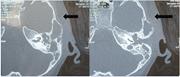

Congenital cholesteatoma presenting with Luc's abscess

Kalimuthu Santhi and others

Journal of Surgical Case Reports, Volume 2012, Issue 12, December 2012, rjs026, https://doi.org/10.1093/jscr/rjs026